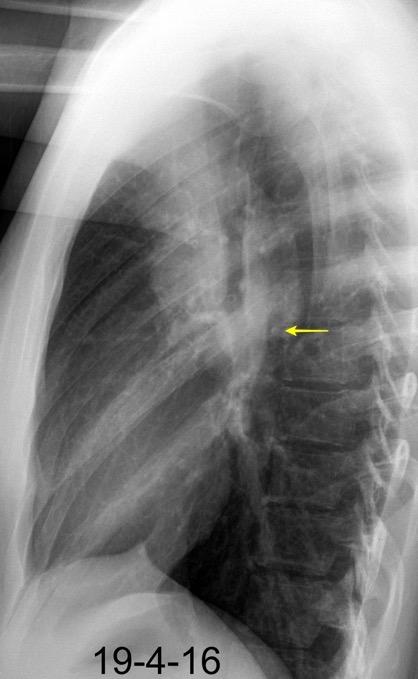

En el normal, el bronquio intermediario (BI) aparece en la proyección lateral, como una línea fina vertical que cruza el bronquio del LSI en su unión con el principal. (BPI) Engrosamiento del bronquio intermediario (BI)

97% de normales

Causas

Fallo cardiaco

Ca de pulmón

Metástasis

Linfoma

Sarcoidosis

Castleman

Schnur MJ et al.. Thickening of the Posterior Wall of the Bronchus Intermedius. Radiology. 1981

MJ et al.. Thickening of the Posterior Wall of the Bronchus Intermedius. Radiology. 1981 Ca. microcítico